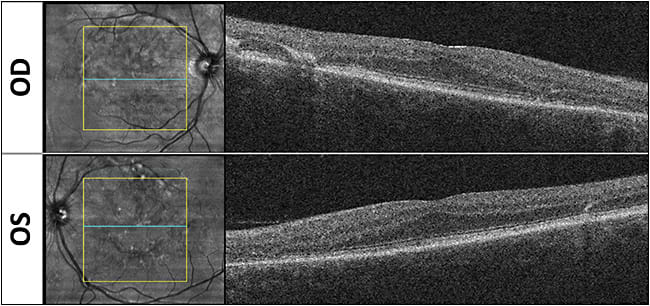

In a recent Retinal Physician Imaging Challenge livestream discussion, I presented a case of a 53-year-old male referred by an outside provider for maculopathy evaluation. Although he denied any family history of vision loss, he endorsed slow decline in vision over years. On examination, his visual acuity (VA) was 20/50 in the right eye and 20/40 in the left, and he had normal intraocular pressures. Anterior-segment examination was significant for a 1+ nuclear sclerosis cataract but otherwise was unremarkable. On dilated examination (Figure 1), we detected scattered yellow-whitish pisciform fundus flecks throughout the posterior pole bilaterally. On fundus autofluorescence (Figure 2), we captured these flecks, which were a mix of hyperautofluoresence (corresponding to increased lipofuscin accumulation) and hypoautofluorescence (atrophy and photoreceptor loss). On optical coherence tomography (Figure 3), some of the flecks could be noted, but there was no intraretinal or subretinal fluid noted. There was also no choroidal neovascularization detected.